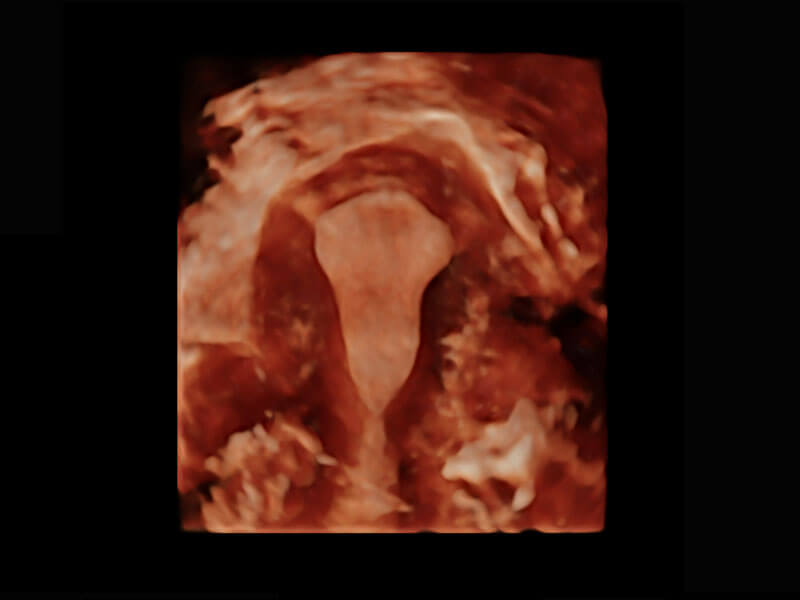

P60優(yōu)異的圖像質(zhì)量搭載專(zhuān)科探頭,在婦科基礎(chǔ)疾病的診斷、卵泡生長(zhǎng)的監(jiān)測(cè)、輸卵管通暢情況的判別等方面為您提供生殖應(yīng)用方案。

腔內(nèi)婦科-宮腔分離

腔內(nèi)婦科-卵巢

腔內(nèi)三維-宮內(nèi)節(jié)育器

腔內(nèi)三維-光影成像